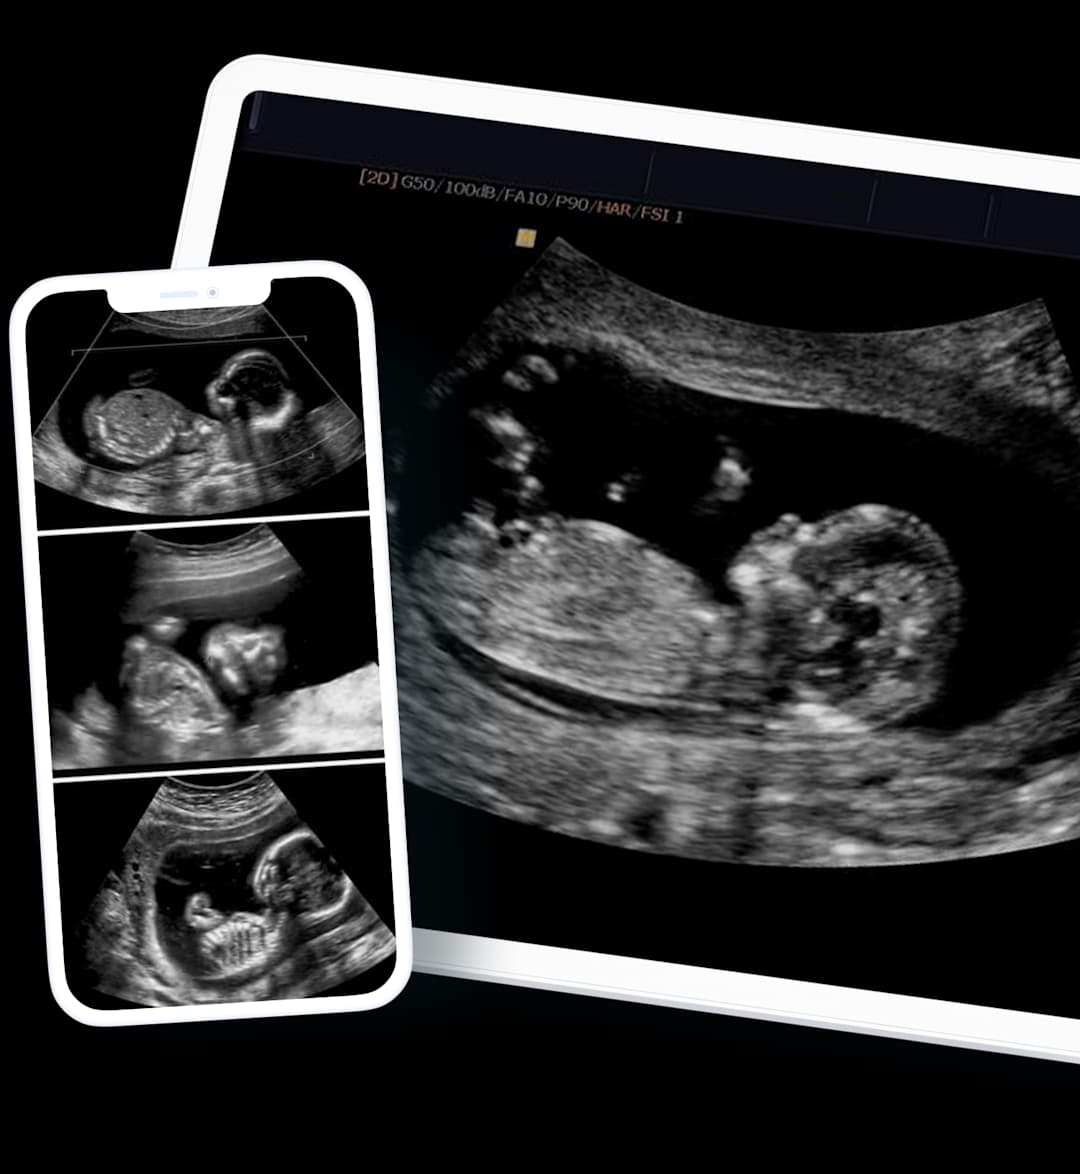

We can provide scan images directly to your smartphone, often on the same day following your appointment. Gain the peace of mind and insight you need, without delay.

Same-Day Results

Timely & Efficient

Share with your Doctor